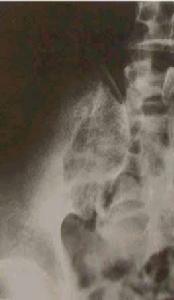

骶髂關節結核--影像檢查時在站立位脊柱前彎、後伸及側彎均受限,並有局部疼痛,但坐位時活動較好。臥位直腿抬高試驗,患側受限並有局部疼痛。壓擠或分離髂骨時患部疼痛,骶髂關節患部有壓痛,可有寒性膿腫或竇道。肛指檢查有時可摸到局部膿腫及壓痛。X線照片檢查對早期診斷很重要,需照骶髂關節正位及斜位(關節的矢狀面),可見骨質破壞、死骨及空洞形成等。

X線攝片早期關節面模糊,邊緣糜爛,關節間隙增寬,晚期關節間隙變窄。並有竇道,常繼發感染。關節呈現硬化。關節破壞嚴重者同側髂骨和恥骨可上移發生病理脫位。